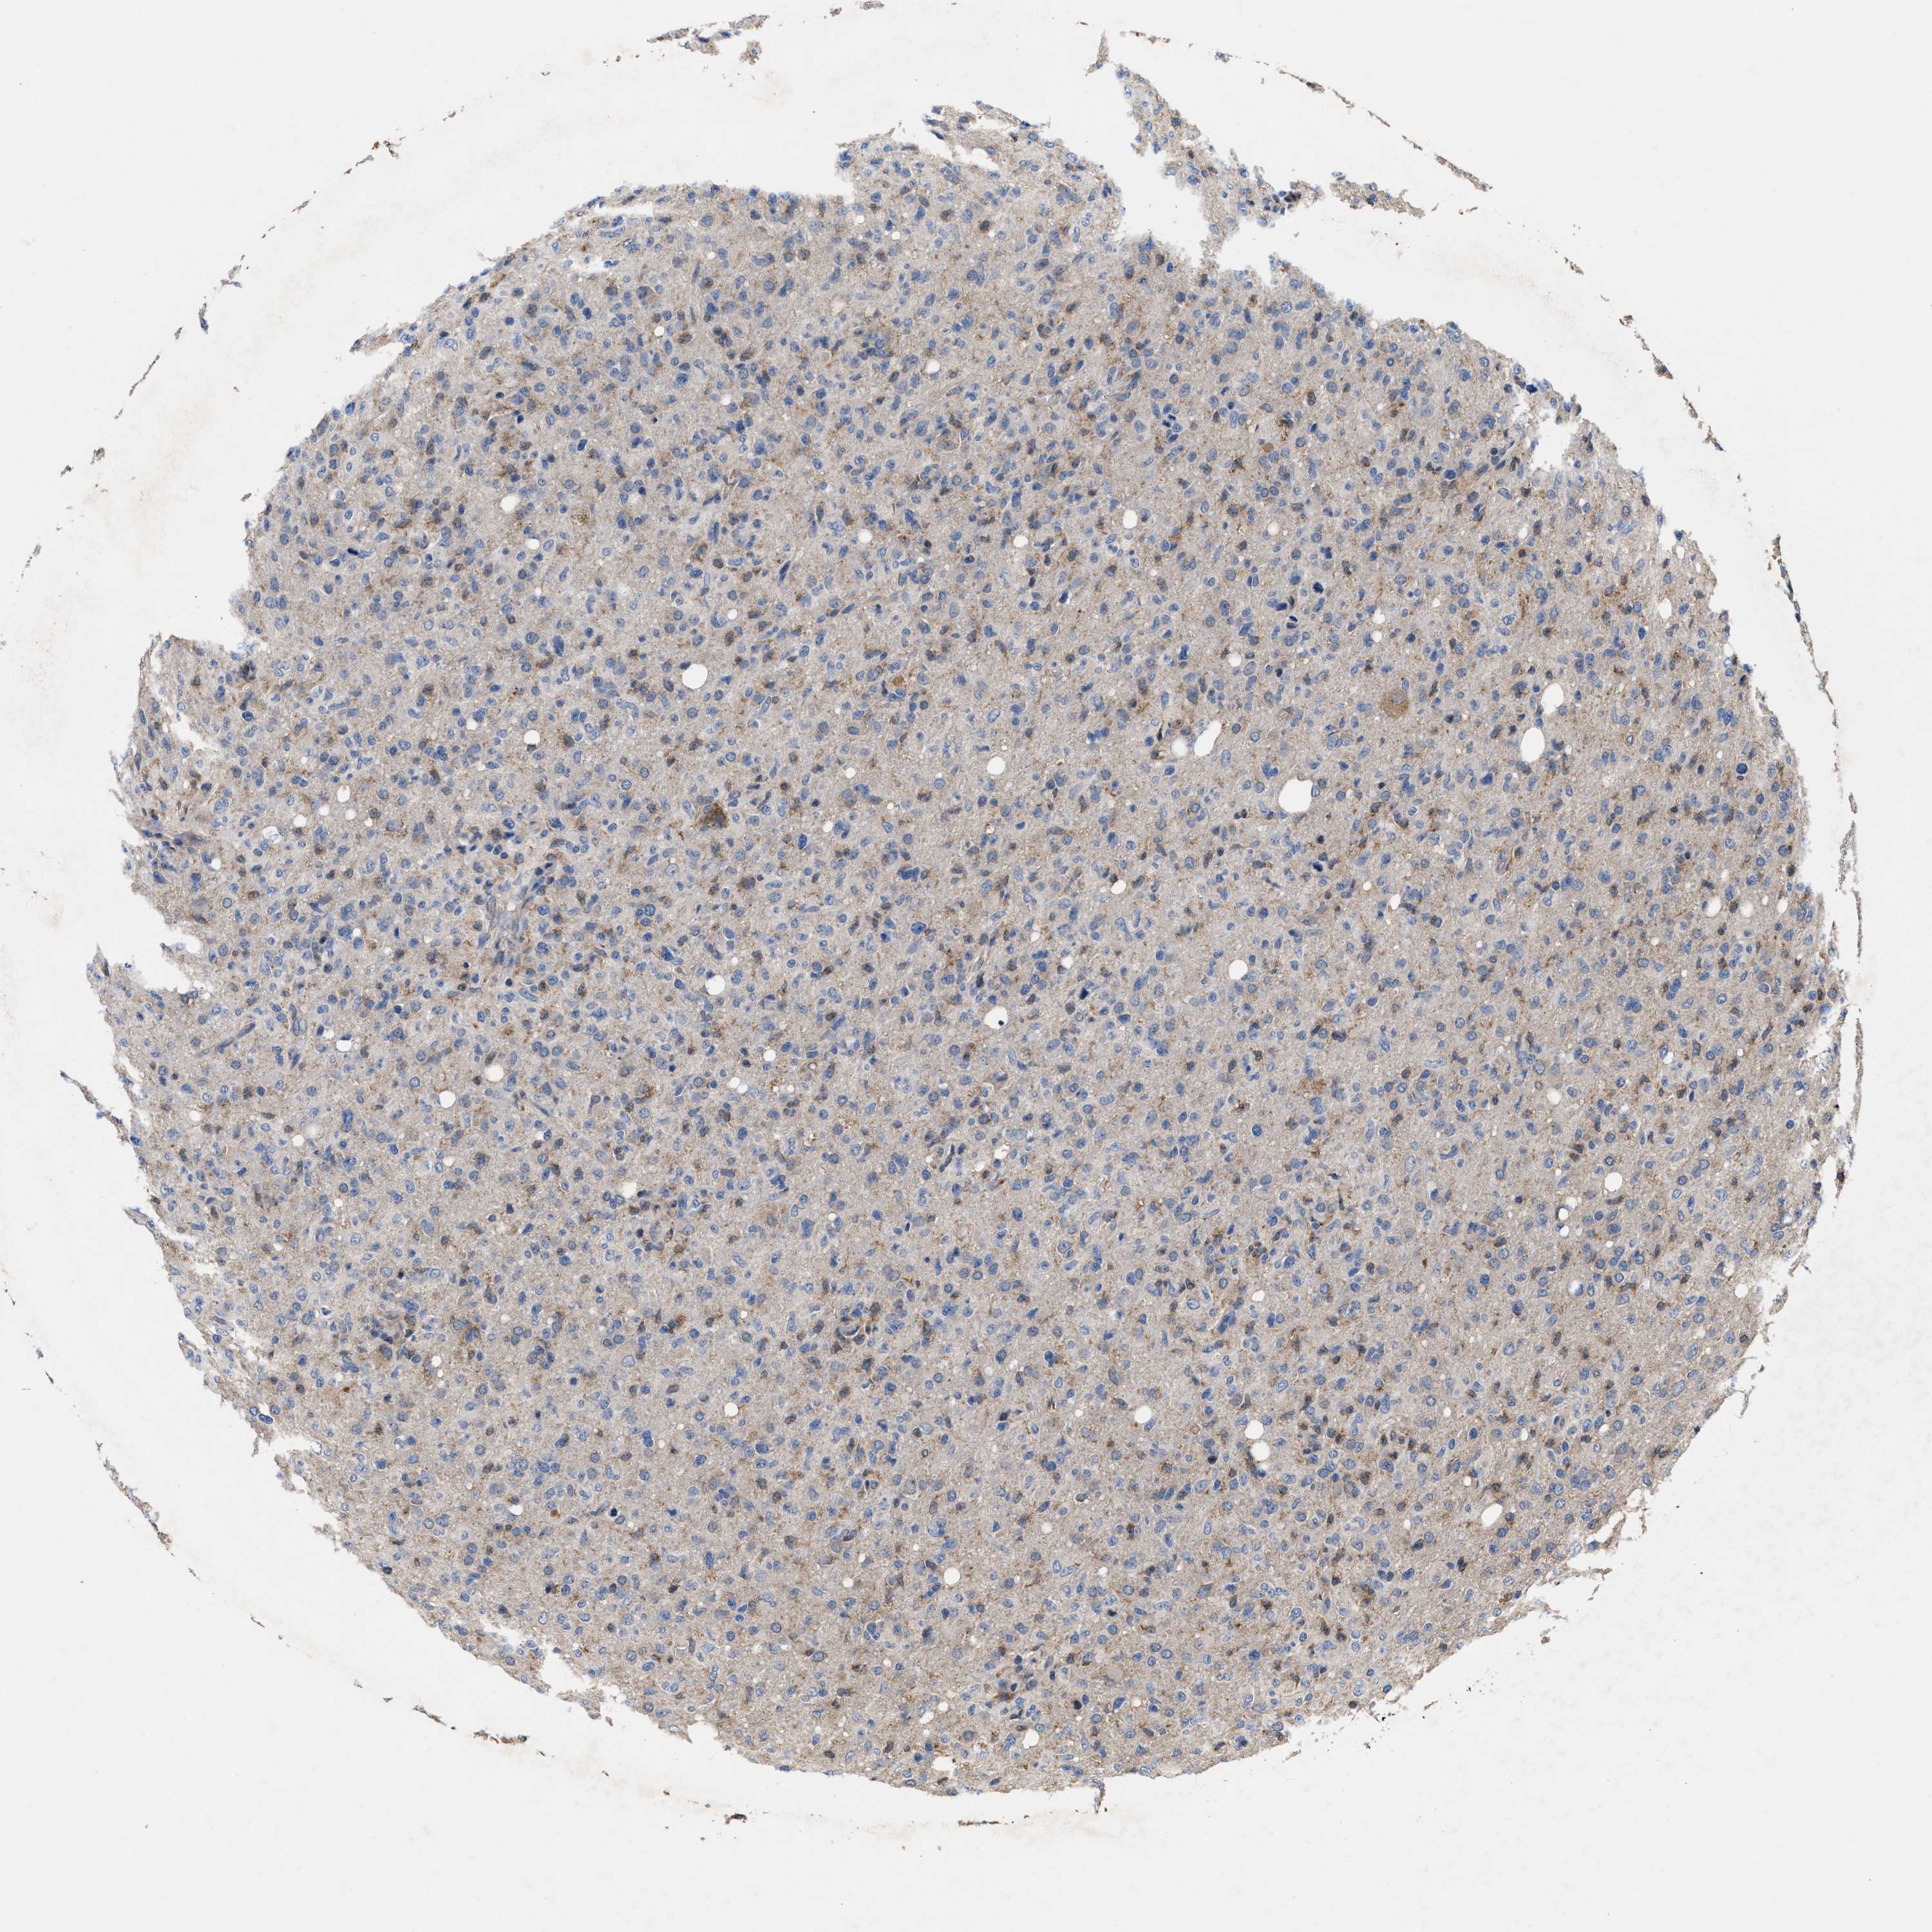

GLIOMA - Protein expressioni

A mouse-over function shows sample information and annotation data. Click on an image to view it in a full screen mode. Samples can be filtered based on level of antibody staining by selecting one or several of the following categories: high, medium, low and not detected. The assay and annotation is described here.

Note that samples used for immunohistochemistry by the Human Protein Atlas do not correspond to samples in the TCGA dataset.

Antibody stainingi

Antibody staining in the annotated cell types in the current human tissue is reported as not detected, low, medium, or high, based on conventional immunohistochemistry profiling in selected tissues. This score is based on the combination of the staining intensity and fraction of stained cells.

Each image is clickable and will lead to virtual microscopy that enables deeper exploration of all samples and also displays staining intensity scores, fraction scores and subcellular localization as well as patient and tissue information for each sample.

HPA022434

HPA022953

HPA022959

HPA028758

CAB007783

Glioma, malignant, High grade

Glioma, malignant, Low grade

Glioblastoma, NOS